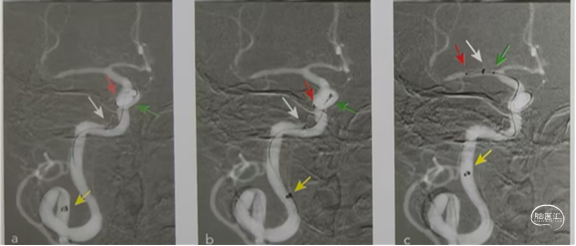

Nueron MAX长鞘开始应置于颈动脉360°环的近端,以避免发生颈动脉夹层(图1)。

沿着微导丝-微导管-抽吸导管组成的三同轴系统,可使长鞘安全地沿360°环向远端推进,通过C1段环状迂曲部位,同时并不会强行改变这种血管迂曲的状态。随后在长鞘高到位支撑下容易将抽吸导管继续向M1段的血栓部位推进。如图所示。